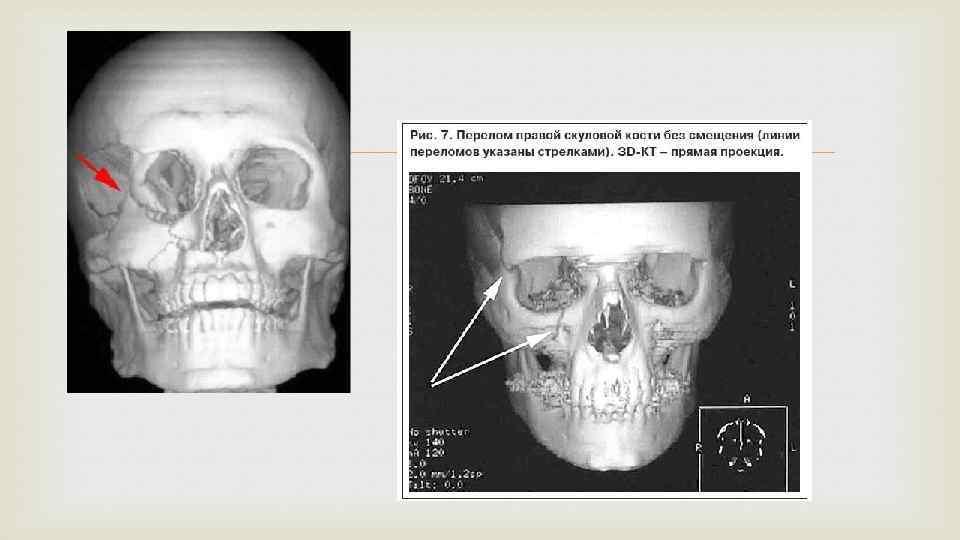

Клиника Для выявления переломов верхней челюсти проводят рентгенологическое исследование челюсти и черепа в разных проекциях, что обусловлено сложностью определения линии перелома, строением верхней челюсти и т. п. Так, при переломе альвеолярного отростка выполняют внутриротовые снимки, переломах скуловой кости — обзорную рентгенограмму в подбородочной проекции, аксиальную и полуаксиальную; для определения нарушения целостности стенок верхнечелюстной пазухи — рентгенограмму околоносовых пазух. Широко применяют ортопантомографию и компьютерную томографию, МРТ, спиральную компьютерную томографию с мультипланарной реконструкцией.